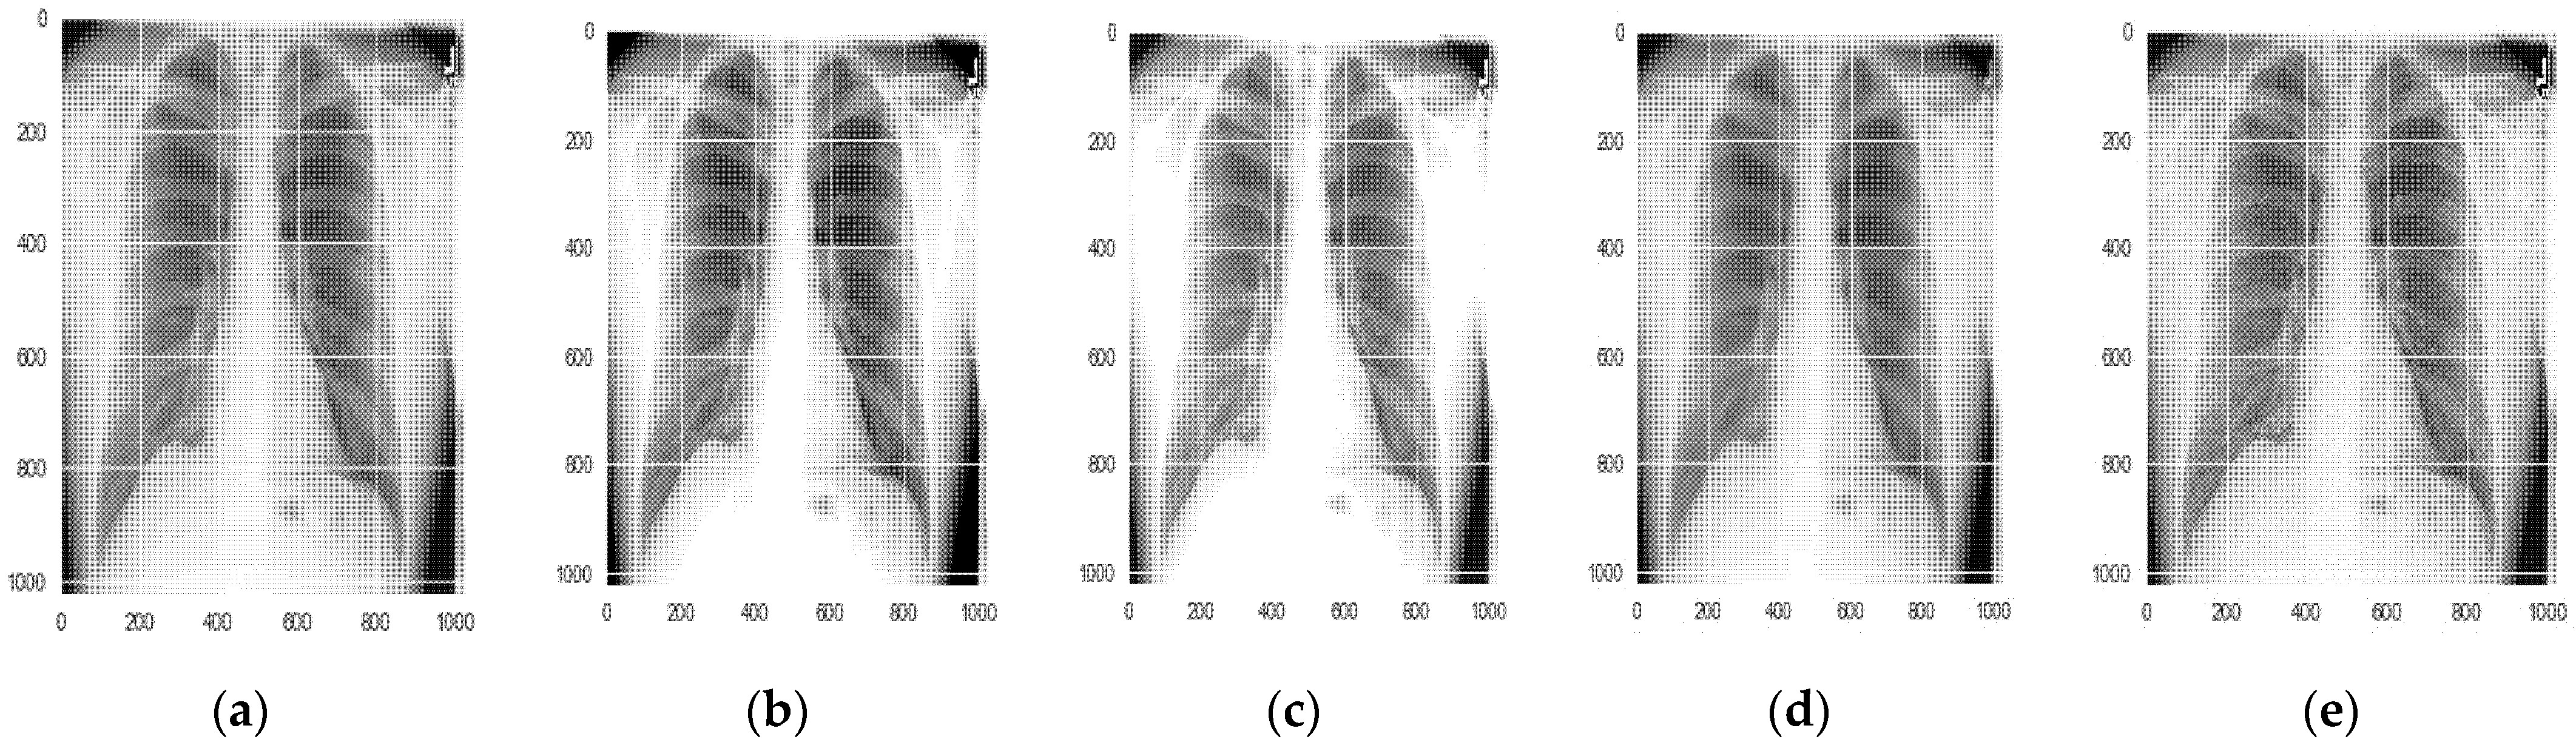

5.1.1. Data Augmentation

6.1. Results for Segmentation of Pneumothorax